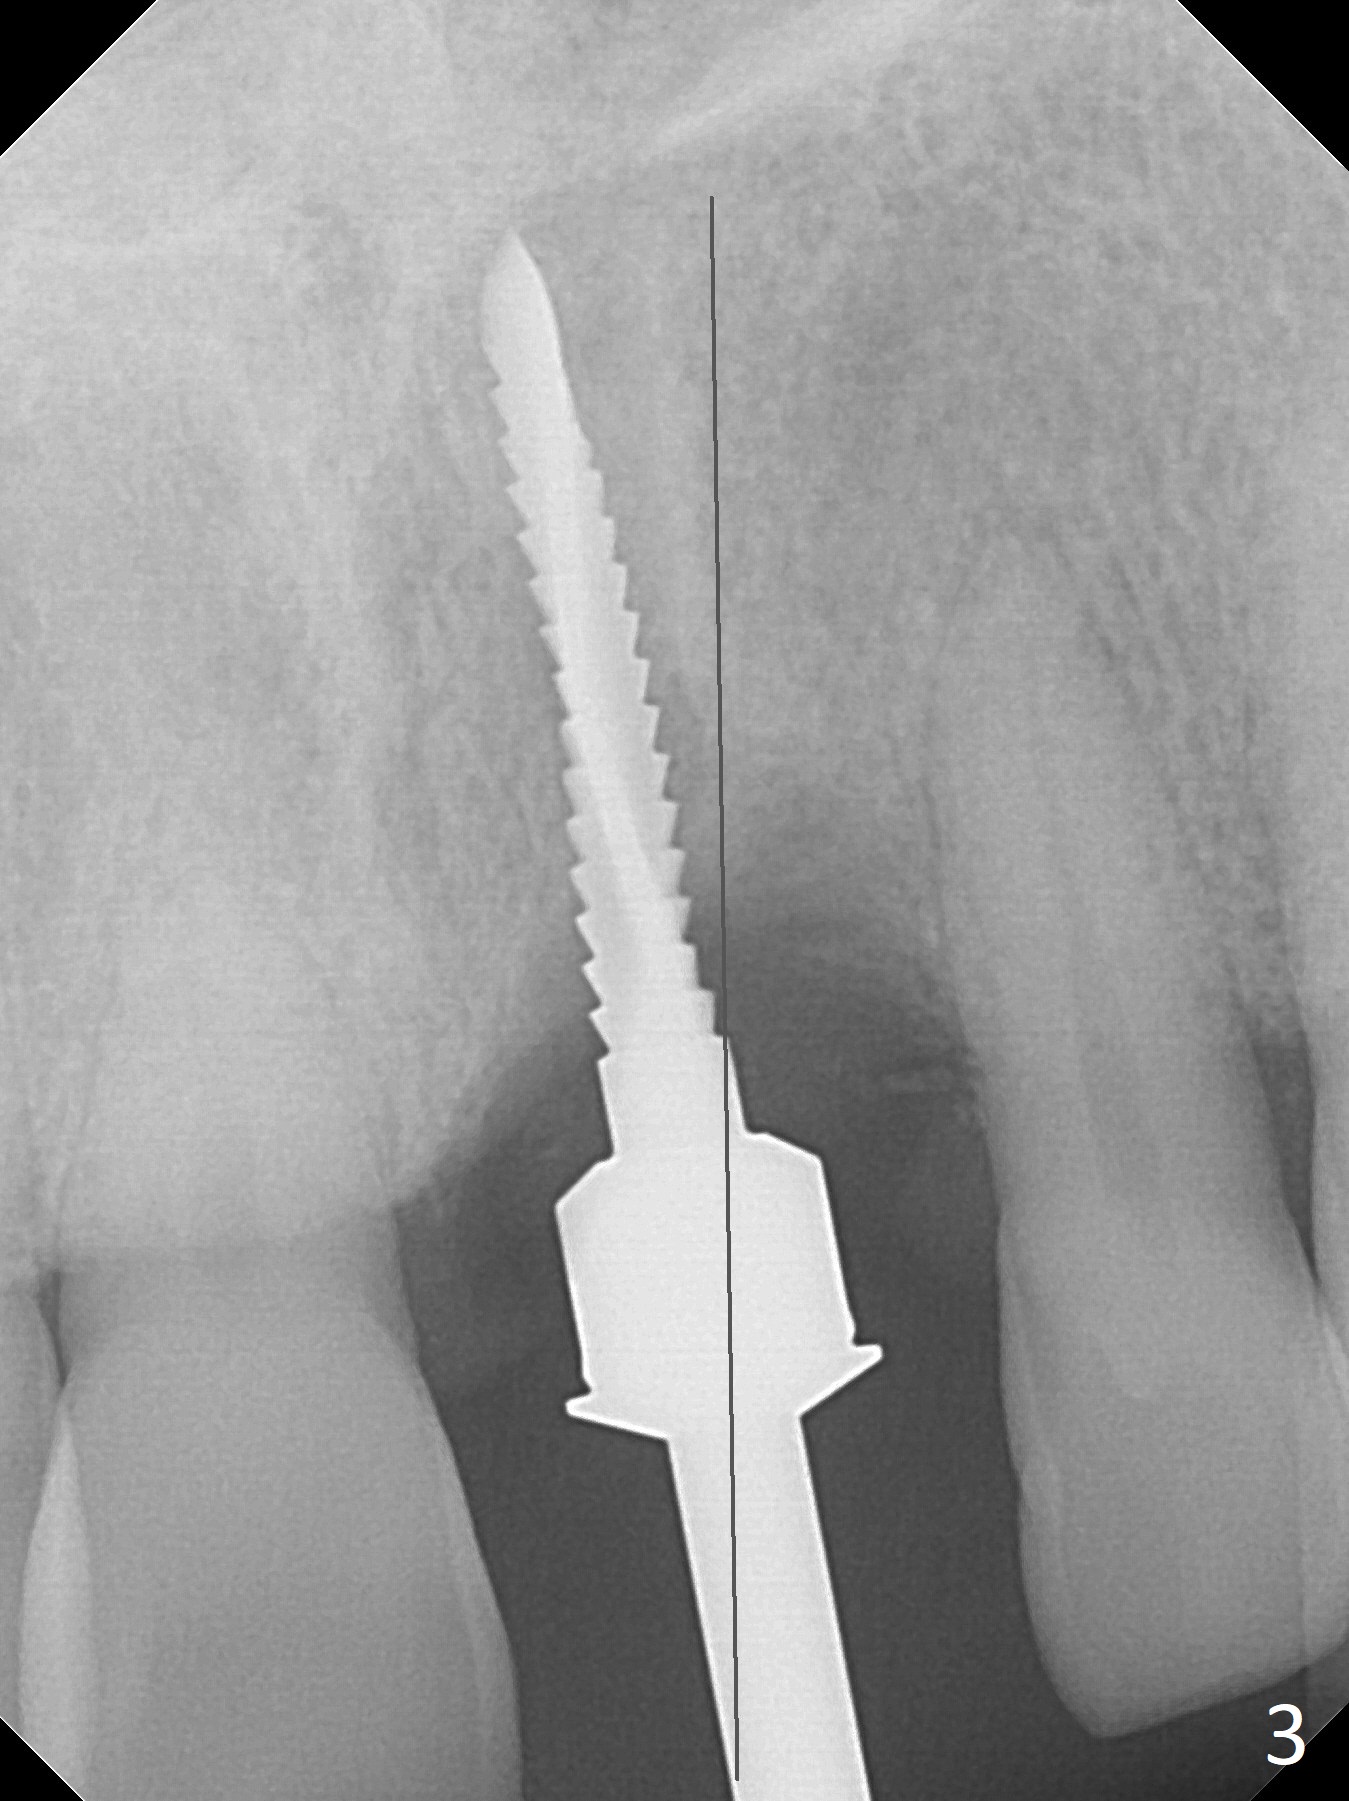

Preop examination shows mobility I of the teeth #8 and 10 and apparent occlusal trauma from #22-26 implant bridge. After occlusal equilibrium, incision reveals low, but moderate ridge at #9 (Fig.1). Fig.2a is a cross section of a normal upper incisor socket with thin buccal plate (B) and thick palatal one (P). It is difficult to initiate osteotomy in the oblique palatal wall when the buccal plate is resorbed (Fig.2b). In this case with horizontal buccal and palatal plate bone loss, the socket bottom is flat (Fig.2c), easy for osteotomy (Fig.2d green arrow, Fig.3). The initial osteotomy deviates mesial (Fig.3). To avoid perforation into the Incisive Canal, the trajectory is changed (Fig.4). After use of the final drill (3 mm), the coronal Incisive Canal is perforated. Following placement of a 3.5x13 mm implant and 4.5x5.5(4) mm abutment, Vanilla Graft is placed (Fig.5 *) to repair the perforation. Retrospectively, the coronal end of the Incisive Canal is revealed at incision (Fig.1 *). The initial osteotomy should be slightly more distal (Fig.3 black line). The buccal plate looks bulky due to placement of the abutment and bone graft 1 week postop (Fig.6,7 (crown dislodgement)). The bone graft appears to remain in place 2 months postop (Fig.8). Impression is taken because of instability of the immediate provisional (Fig.9 after Laser gingivectomy). The gingiva and buccal plate remain healthy 4.5 months postop (Fig.10). A permanent crown is cemented (Fig.11).